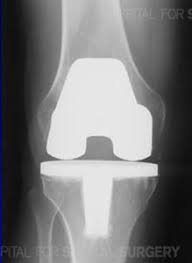

Total Knee Replacement

October 9, 2004 "What man is he that fears the Lord? Him shall He teach in the way that He shall choose." Psalm 25:12 (KJV) If the Lord tarries, my total knee replacement surgery will be on Monday, November 8. I visited three rehabilitation (rehab) facilities and chose the nicest one with a private room… Continue reading Total Knee Replacement